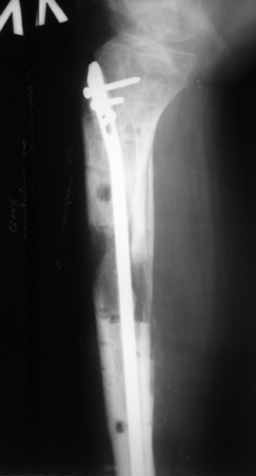

В случае гладкого заживления раны, при условии положительного решения вопроса с металлом, планируем перемонтаж аппарата Илизарова, дополнительную резекцию дистального отломка, выведение полокости голеностопного сустава в правильное положение (см. боковую Р-грамму), одномоментно остеотомия большеберцовой кости. После восстановления длинны голени, по всей видимости, артродез голеностопного сустава.

Рентгенограммы прилагаются. Фото местного статуса выложу в ближайшее время.

Ерсин, мы тоже имеем опыт такой фиксации. Подобную операцию за последние 3 года мы сделали трем пациентам. Снимки одного из них я прилагаю.

К сожалению, ни в одном из этих 3-х случаев мы не получили удовлетворяющего нас результата. Очень трудно провести штифт, введенный антеградно ровно по центру таранной кости. Отсутствие подвижности между диафизом и дистальным отломком большеберцовой кости (после фиксации в аппарате в течение 1-2 мес) очень усложняет проведение штифта в центр блока таранной кости. Поэтому мы от этого пока отказались, и проводим штифт через пятку. При данном варианте фиксации подобных проблем не возникало ни разу.